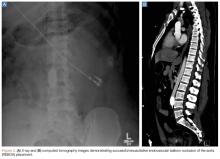

Most recently, REBOA has been used for noncompressible torso hemorrhage following trauma. This method involves percutaneous arterial cannulation of the common femoral artery and advancement of a balloon into the aorta, where it is then inflated at the desired level.

Depending on suspected or known location of the source of hemorrhage, this is either just proximal to the diaphragm (zone 1), or just proximal to the aortic bifurcation (zone 3). (See Figures 2a and 2b for an example of successful REBOA placement.)Once inflated, the balloon obstructs arterial inflow to the area of hemorrhage, curtailing blood loss, and increases proximal BP, improving coronary and cerebral perfusion. Multiple case reports and case series have described successful use of REBOA for hemorrhage control, including prehospital use by physicians in the United Kingdom. The largest series to date looked at 114 patients, of whom 46 had REBOA placement and 68 had open aortic occlusion through resuscitative thoracotomy.45 Those treated with REBOA were significantly more likely to achieve hemodynamic stability (defined as SBP >90 mm Hg for >5 minutes). Furthermore, the authors noted minimal complications from REBOA and no difference in time to successful aortic occlusion, regardless of technique. There was also no difference in mortality between the two groups. Despite the small number of studies in trauma patients, REBOA has been established as a viable alternative to open aortic occlusion. The prospective Aortic Occlusion for Resuscitation in Trauma and Acute Care Surgery registry established by the American Association for the Surgery of Trauma is continuing to enroll patients and will hopefully answer many of the current uncertainties regarding the use of REBOA.